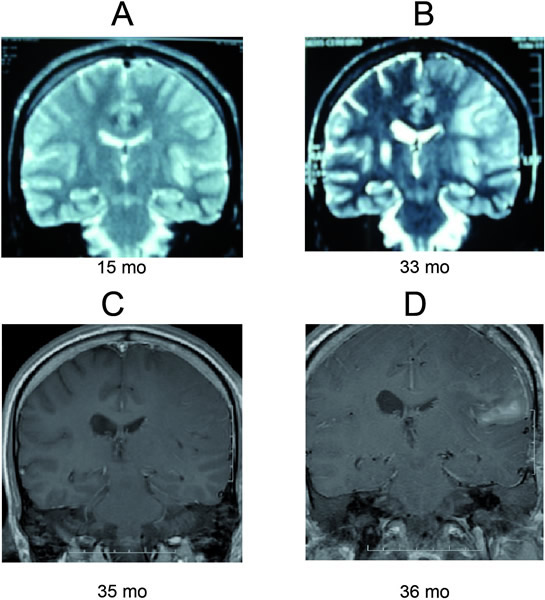

Rationale: Rasmussen s encephalitis is a rare, chronic, progressive disease that typically appears in childhood. Today, the only effective therapy is a hemispherectomy; however, this procedure is associated with irreversible neurological deficits. Novel therapeutic approaches for this condition are, therefore, necessary. One candidate might undergo cathodal direct current transcranial electrical stimulation. Methods: We describe a case of a patient with late-onset Rasmussen s encephalitis treated with transcranial electrical stimulation. The therapy was transferred by a disposable subdermal needle 12mm in length, and is 0.4mm diameter (27 gauge; cathode) and typical golden cup electrode (anode), delivered by Nicolet Endeavor CR (VIASYS Healthcare, USA) with a maximum safety output of 2 mA. The site for stimulation was determined by the EEG electrode 10-20 system based in a previous study. A constant current of 1 mA intensity was applied to the scalp (C3 (-/cathodal)/contralateral supraorbital area ( /anodal)) for 60 minutes in four sessions (0, 7, 30 and 60 days). Results: A 30 year-old male with late-onset Rasmussen s encephalitis underwent a constant current transcranial electrical stimulation of 1 mA intensity for 60 minutes in four sessions (0, 7, 30 and 60 days). Any complications were observed during the therapy. In the follow up, 6 months later our patient becomes seizure free, improved alert state and global aphasia. Conclusions: In the transcranial electrical stimulation, a weak constant electric current is injected into the brain via two large scalp electrodes. This weak current induces a change in membrane threshold (hyper or de-polarization) that results in focal changes of cortical excitability increase or decrease depending on the electrode polarity that lasts beyond the period of stimulation, modulating the cortical excitability in the human motor, prefrontal, and visual cortex. This is the first time that transcranial electrical stimulation has been used in serial sessions to treat Rasmussen s encephalitis and avoid or delay surgical treatment.